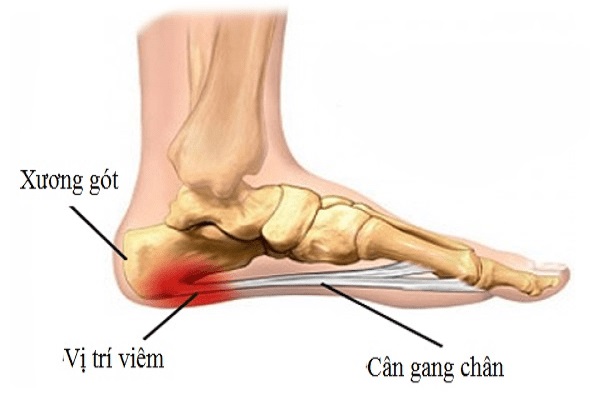

Viêm cân gan chân

Đây là hiện tượng viêm sưng vùng cân gan chân tức là phần mô dày ở dưới lòng bàn chân kéo dài từ gót đến ngón chân. Viêm cân bàn chân cũng giống như các loại viêm trên đều do người chơi thể thao luôn chịu những sang chấn trường diễn tại một vùng.

Những người bị căng cơ và vòm gan chân cao dễ mắc phải viêm cân gan chân. Mặc dù nguyên nhân gây ra chứng bệnh này có thể liên quan đến hoạt động quá sức. Nếu chạy bộ quá sức của mình hay chạy quá nhanh, triệu chứng đau gan bàn chân (vùng trũng nhất của bàn chân) là điều khó tránh khỏi do chân phải luôn co, duỗi liên tục. Tuy nhiên, viêm cân gan chân cũng có thể xảy ra dù không có lý do rõ ràng nào cả.

*Cách chữa trị: cách chữa trị tốt nhất là nghỉ ngơi, duỗi thẳng và co giãn bắp chân để tránh hiện tượng co cơ, chườm đá vào lòng bàn chân.